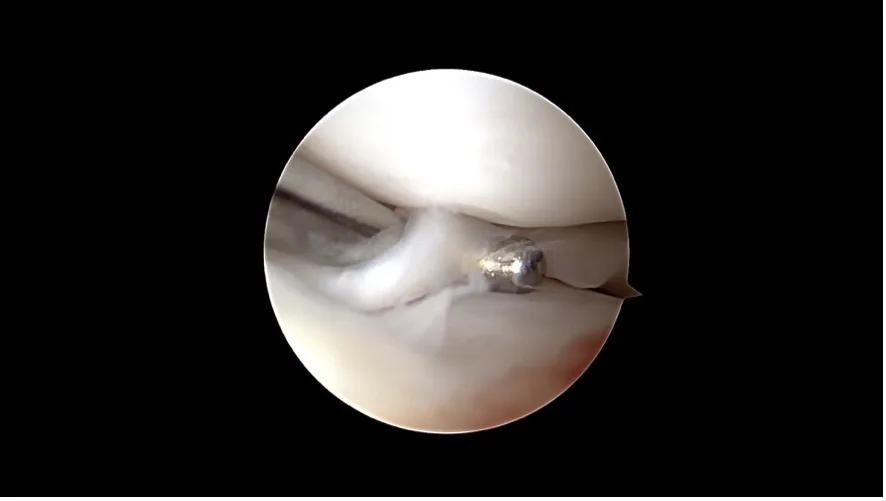

Ein kompletter Kreuzbandriss

Arthroskopie: Diese Technik ermöglicht eine direkte Sicht auf das Gelenkinnere mit Hilfe einer kleinen Kamera. Über nur wenige Millimeter grosse Hautöffnungen lassen sich Veränderungen am Kreuzband sowie begleitende Schäden wie Meniskusrisse erkennen und in vielen Fällen auch direkt behandeln.

Korbhenkel-artiger Meniskus Riss

Nanoskopie: Noch feiner als die Arthroskopie bietet die Nanoskopie die Möglichkeit, mit besonders kleinen Instrumenten und hochauflösender Bildtechnik im Gelenk zu arbeiten. Das Verfahren ist besonders geeignet für kleinere Hunde. Beide Methoden sind minimalinvasiv, verursachen wenig Gewebetrauma und ermöglichen eine schnellere Erholung.